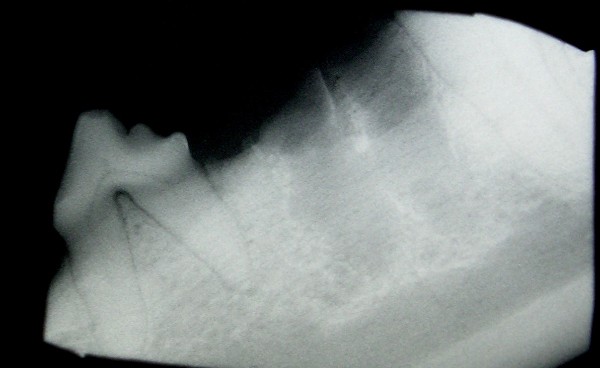

Die spezielle Untersuchung bestätigte den Befund. Das „Bläschen“ stellte sich als Fistelöffnung dar, aus welcher sich eitriges Sekret entleerte. Obwohl der Zahn nicht beschädigt zu sein schien, bestand der Verdacht auf eine Veränderung im Bereich der Zahnwurzeln. Tinka wurde in Narkose gelegt um eine Röntgenaufnahme anzufertigen. Ein röntgensichtbares Guttaperchastiftchen wurde ca. 10mm tief in die Fistelöffnung eingelegt um den Ursprung und Verlauf des Fistelganges darstellen zu können.

Die Röntgenaufnahme wurde in lateralem Strahlengang ausgeführt. Zu sehen ist das sich weiss darstellende Guttaperchastiftchen , dessen Spitze bis zum unteren Drittel der vorderen Wurzel geschoben werden konnte. Beide Wurzeln waren durch Resorption in ihrer Form stark verändert (rote Kontur). Der gesamte Knochen im Bereich der Zahnwurzeln war durch Osteolyse zerstört (schwarze Kontur).